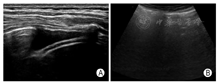

(1)将探头置于BLUE-PLUS方案确定的5个标准位点的肋间,然后于各位点进行横向(探头平行于肋间隙,图3A)和纵向扫查(探头垂直于肋间隙,图3B)。进行PLAPS点的扫查时探头方向指向前胸胸骨方向为宜。同时可以对照患者CT所提示病变区域所在体表投影区域对应扫查,标记并存图。

横向扫查时,显示光滑胸膜线,至少显示2条水平方向的A线;纵向扫查时表现为"蝙蝠征"(两侧肋骨声影与之间胸膜线构成)。正常肺部图像应显示胸膜线、A线,能够观察到肺滑动征(图4)。